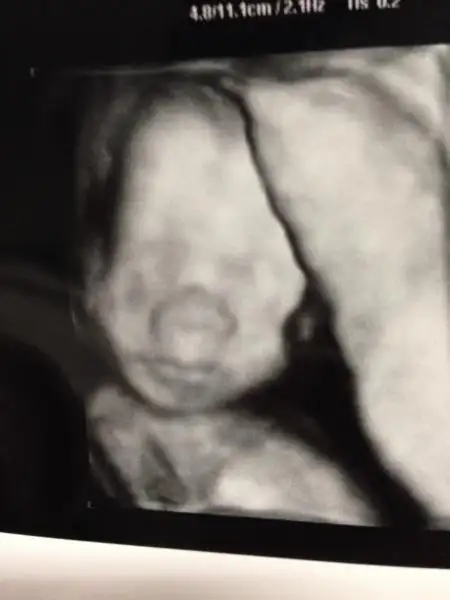

Dün detaylımız vardı, kızım kocaman olmuş ilk kez yüzünü gördüm aynı babası :1:

Her şeyi normal çok küşür, röntgen doktorumuz çok kibardı ve her detayı anlattı bize. Göbek bağında 3 damar olmalı o var, kalp 4 odacıktan oluşmalı oluşmuş, idrar torbasında idrar var bu böbreklerin iyi olduğunu gösterir ( ben o anda idrar salgılıyor mu diye sordum doktor evet dedi. Kocamla aynı anda şok olup nasıl yani çişini yapıyor mu nereye yapıyor dedik, doktor da güldü kesesinin içine yapıyor kesesi sirkülasyonla temizlenior dedi. Ay kuzucum çişli suyunda duruyor hatta bide onu yutuyor:1: )

Kilosu 624 gr, kafası biraz büyükmüş, koca kafalı kızım ( babası da koca kafalı ama kabul etmiyor :27: )

Burnu büyük görünür ona aldırmayın daha düzenlenecek küçülecek dedi doktor ( herkes kendi bebeği için niye böyle patlıcan gibi kocaman burnu var diye soruyormuş, normalmiş bu arkadaşlar, şuan şişmiş, kendi bebeğiniz için böyle düşünürseniz diye detay vereyim dedim )

bu da kızımın yüzü maşallah deyin teyzeleri

Eki Görüntüle 995071 Eki Görüntüle 995072